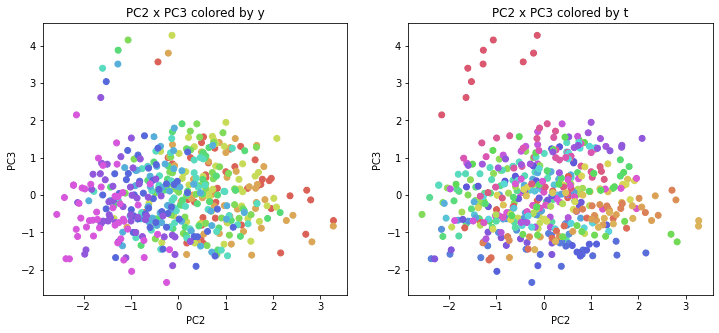

PCAの結果の第n主成分をPCnと表記します。

医療費データの場合と同様に、PCAの結果を見やすく表示するため、seabornのカラーパレットを使って、年月別、都道府県別に色分けして図示してみます(左側が年月別に色分け、右側が都道府県別に色分け)。PC1~PC8まで表示しました。

医療費データの場合ほどはっきりとはしていませんが、PC2が概ね時間の経過を表す成分で、残りの成分が時点によって変わらない地域の特徴を表す成分となっているようです。

また、PC1×PC3を見ると、47沖縄が他の都道府県からかなり離れたところに位置しており、沖縄の地域差が際立っているのが分かります。これは、以前別の記事で年齢階級のない健診データでPCAを実行した場合と似た結果となっています。

今回は、医療費データと同様に、健診データ240次元についてPCAを実行してみました。PCAの結果、医療費データの場合ほどはっきりしとはしていませんが、第2主成分が概ね時間の経過を表す成分で、時間軸に沿った全体的な動き(全国的な動き)を表しており、それ以外の成分が地域の特徴を表す成分で、この10年間あまり変わっていないことがわかりました。